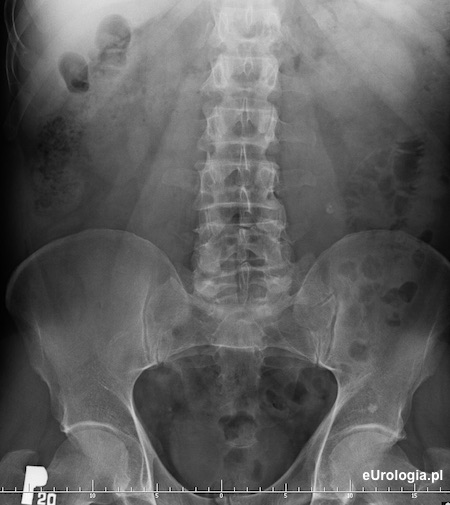

Urografia - kamica górnego odcinka lewego moczowodu

Cień wapienny w rzucie lewego moczowodu na wysokości przestrzeni międzykręgowej L3/L4 po stronie lewej